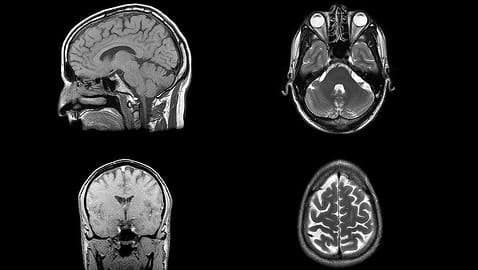

Scans of the patients' brains made both before and after treatment showed that those who were given the placebo had seven times greater levels of brain dementia than those who were given B vitamins.